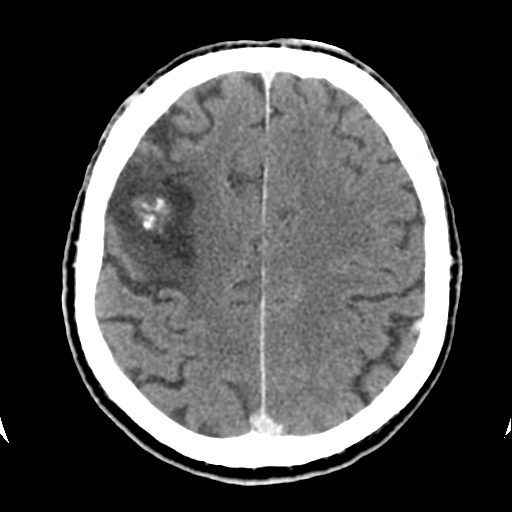

Образование головного мозга КТ.

Привезли с неврологическим дефицитом и эпи экстренно. До и после контрастирования картина образования практически не изменилась.

А по плотности - внутри  кальцинаты?

Ага, кальцинаты...

Даю намётку! Локально - атрофия, желудок ползет в зону структурных изменений (это по поводу опухоли если говорить - не отек). Травм не было.

кавернозная ангиома ?

Вообще-то зона пониженной плотности вокруг - это старые изменения, кистозно-глиозные... Что за кальцинированная блямба в центре - непонятно. Контраст не копила?

Я ничего не утаиваю. Анамнеза другого не знаю, травм не было вообще, кости не изменены.  ОНМК по клинике невролог ставит и эпиприпадок по клинике перед тем, как его привезли.

В общем что я сам думаю по этому поводу...

Конечно, это не глиальная опухоль, к.м.к. и не мтс. Естественно, про отек тут речь не идет, вокруг зона кистозно-атрофических изменений с глиозом. Ну что может быть? Если есть зона мертвой ткани, значит был ишемический инфаркт/кровоизлияние. Травмы исключает, никаких признаков. Дык вот мое мнение, что это образование - какая-то небольшая КА, АВМ (что-то сосудистое), которое либо тромбировалось, либо произошло кровоизлияние и эта дрянь сама от себя погибла и поставила себе надгробья в виде таких камней. Как вам такой расклад? Только не говорите, что я курю что-то злое devil Просто других объяснений не вижу.

Вообще, если мы видим образование повышенной плотности с кальцинатами, не накапливающее контраст, то логичнее всего подумать о кавернозной ангиоме. Хотя эти штуки обычно никак себя клинически не проявляют, и мозговая ткань вокруг них обычно не изменена.